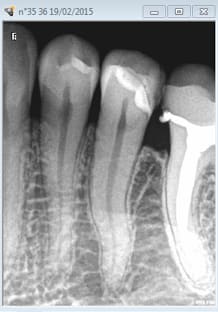

Aie 9 ans aussi. Ouh lalalala la cata. J'aurais du faire des radios après la pose il y a un binz en distal de la 36. -)))